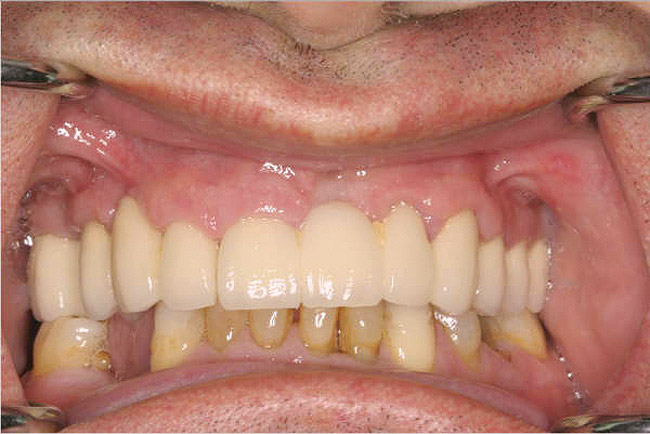

Fixed Restorations: Large Segment/Full Arch

For large-segment/full-arch fixed prostheses, the critical distance is 15 mm. If the distance from the implant platform to the occlusal table is less than 15 mm, then the prosthetic material indicated is porcelain-fused-to-metal (PFM) (Figure 3). If the distance is greater than 15 mm, then a hybrid prosthesis should be used (Figure 4).

The 15-mm measurement is important because of the physical properties of the restorative materials. Acrylic requires bulk for strength. If there is less than 15 mm of distance from the implant platform to the occlusal table, there will not be sufficient space to achieve the bulk of acrylic necessary to provide strength for the prosthesis. The unfortunate result will be continual repair of fractures for the life of the prosthesis.

Likewise, PFM restorations have difficulties when too much space is available. At dimensions greater than 15 mm from the implant platform to the occlusal table, the control of surface porosity across the metal substructure becomes difficult because of variations in cooling and heating rates across the metal,10 which in turn makes it difficult to bake porcelain to the metal substructure. The result is the high possibility of future unwanted complications of porcelain fracture.11

There is also a considerable difference in the laboratory costs for these types of prostheses. A PFM restoration requires more metal to achieve a uniform 2-mm thickness and is more technique-sensitive (Figure 5 and Figure 6). A hybrid prosthesis requires less metal and uses acrylic and denture teeth for the remaining restoration (Figure 7 and Figure 8). Understanding the impact that the 15-mm height has on which type of restoration is required gives the dentist the ability to quote a more accurate fee to the patient.

Figure 3   A crown height space < 15 mm necessitates a PFM material selection.

Figure 3

Figure 4  A crown height space > 15 mm necessitates a hybrid restoration.

Figure 4